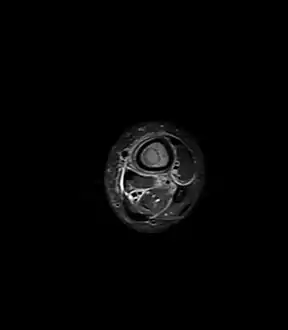

Axial T1-weighted fat-saturated MRI image following IV gadolinium contrast demonstrating the intramedullary lytic area seen on radiography to be ring enhancing consistent with a purulent fluid collection. Extensive circumferential periosteal enhancement is noted. There is also substantial bone marrow enhancement.